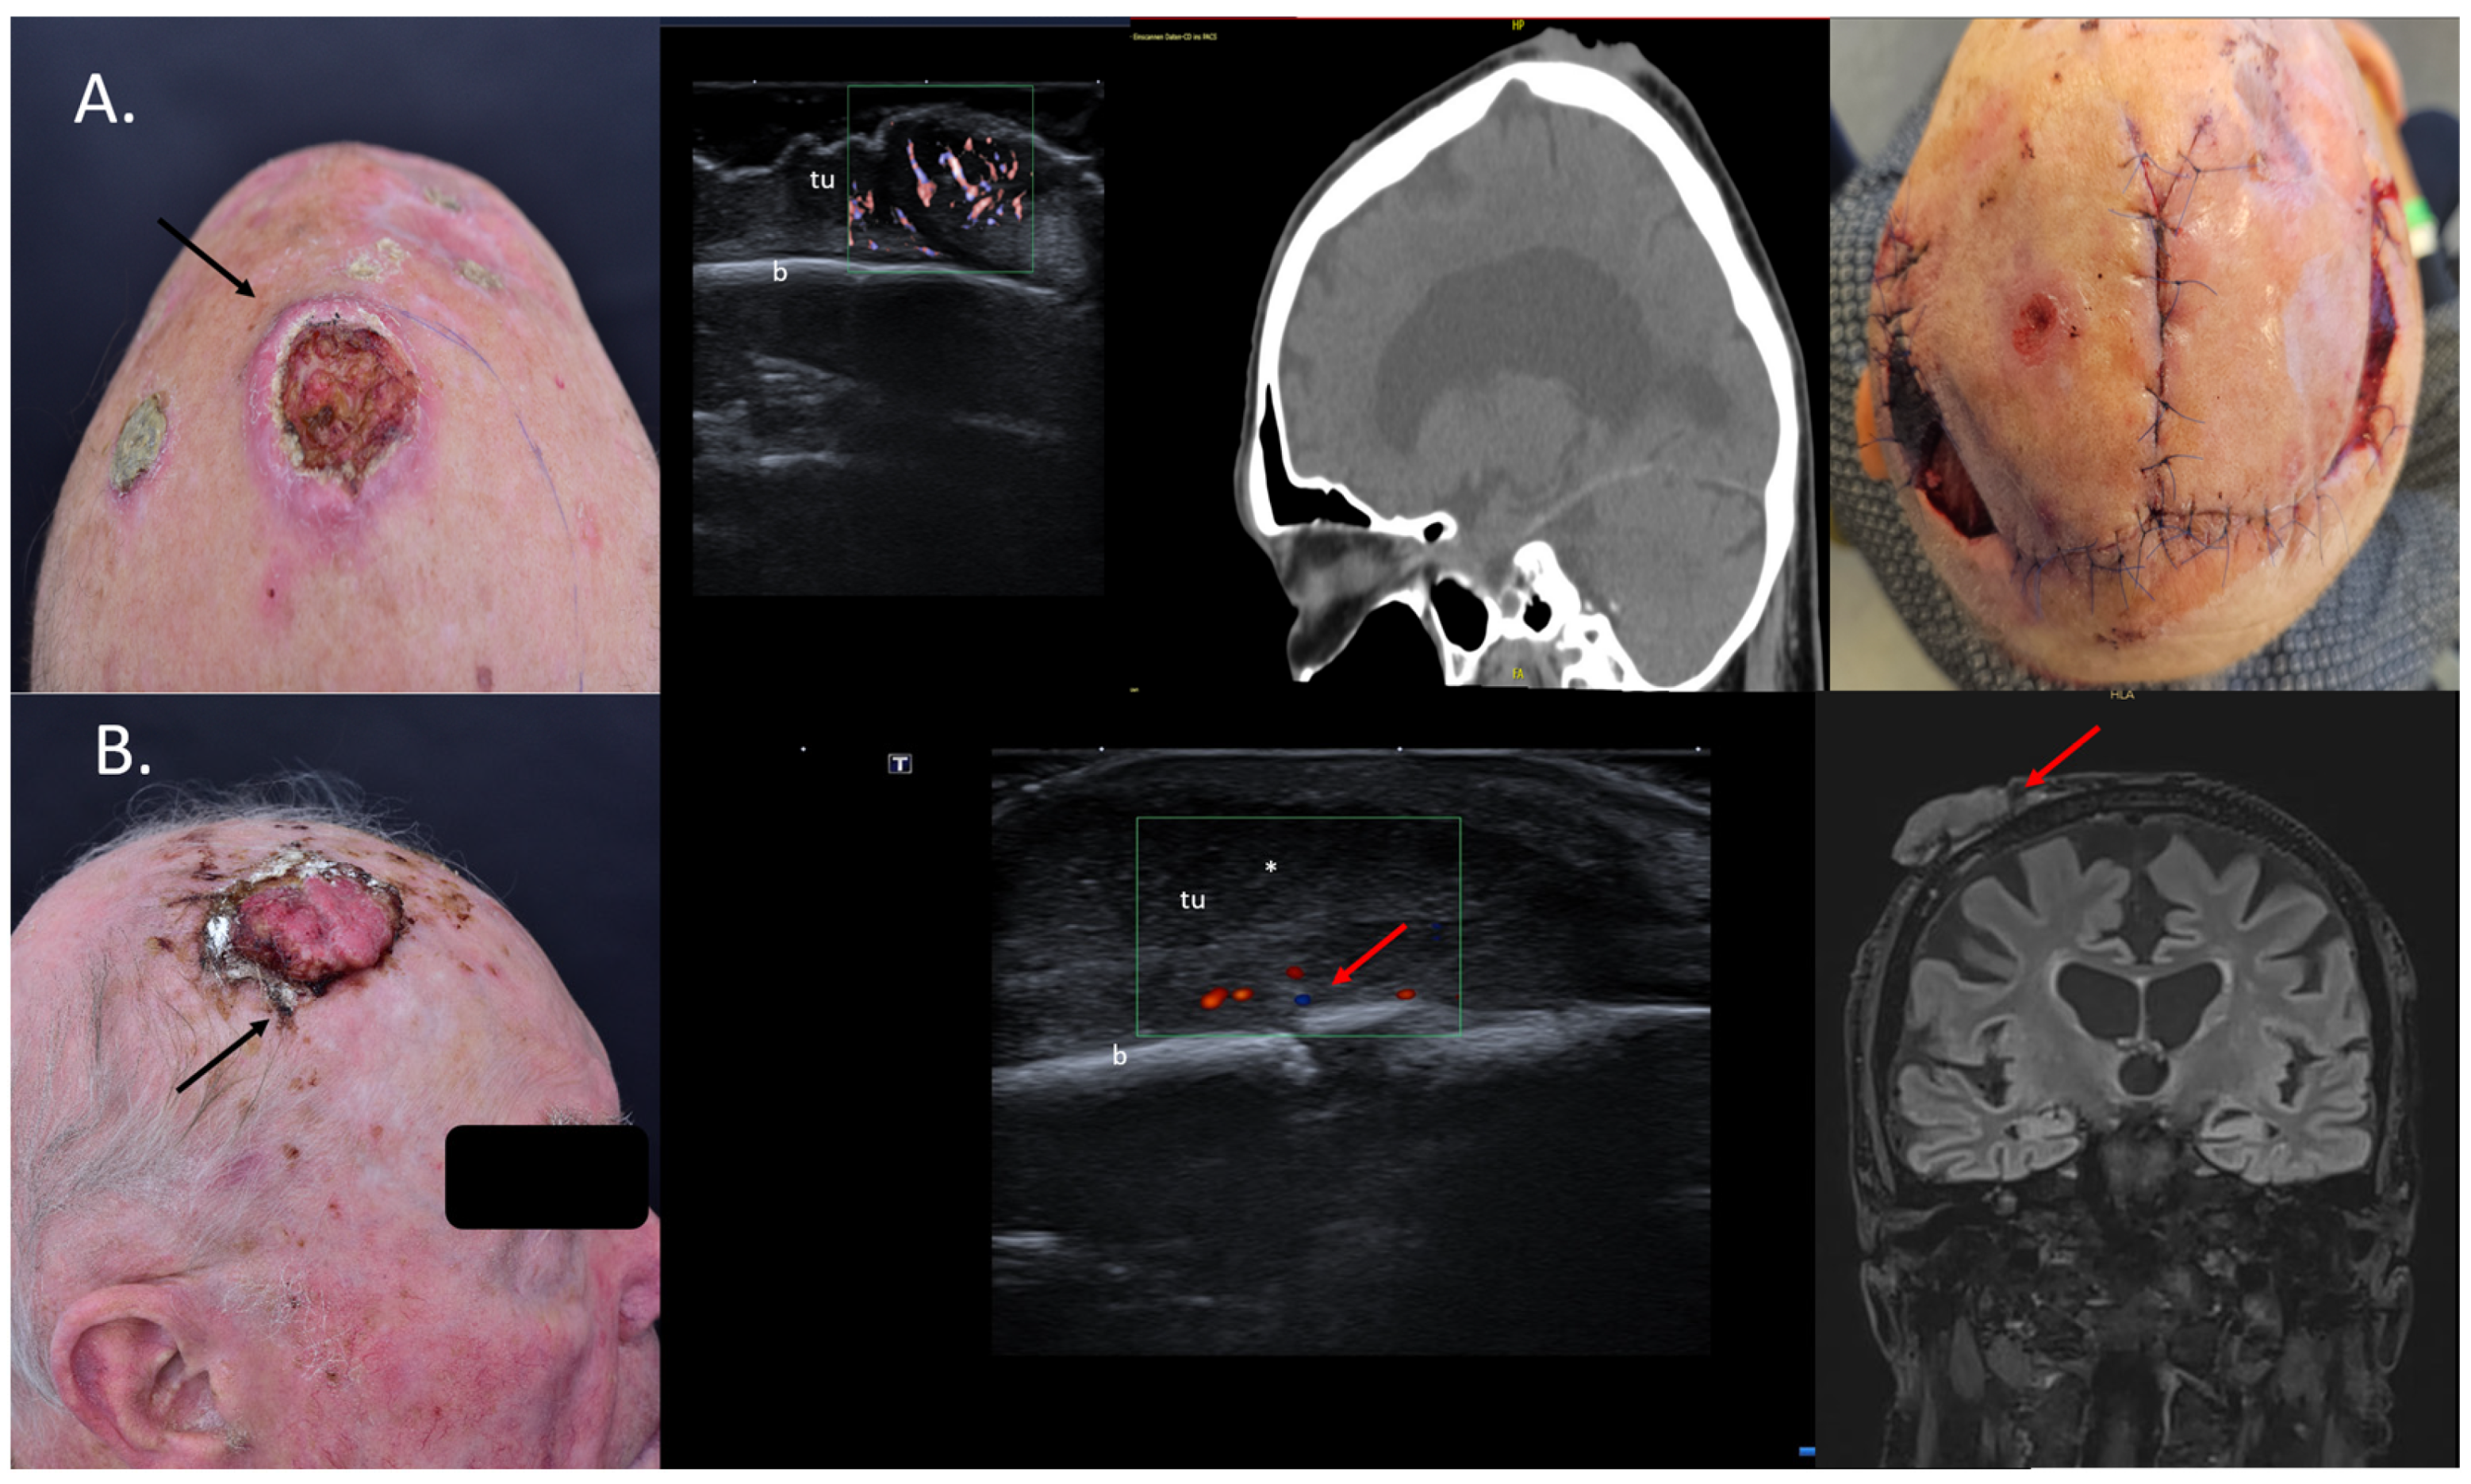

4. Assessment of the Tumor Infiltration Depth

5. Tumor Mapping and Evaluation of Operability

6. Identification of Cases for Mohs Surgery

7. Choice of Surgical Approach

10. Avoidance of Unnecessary Surgeries due to Patient Up-Staging

11. Intraoperative Guidance